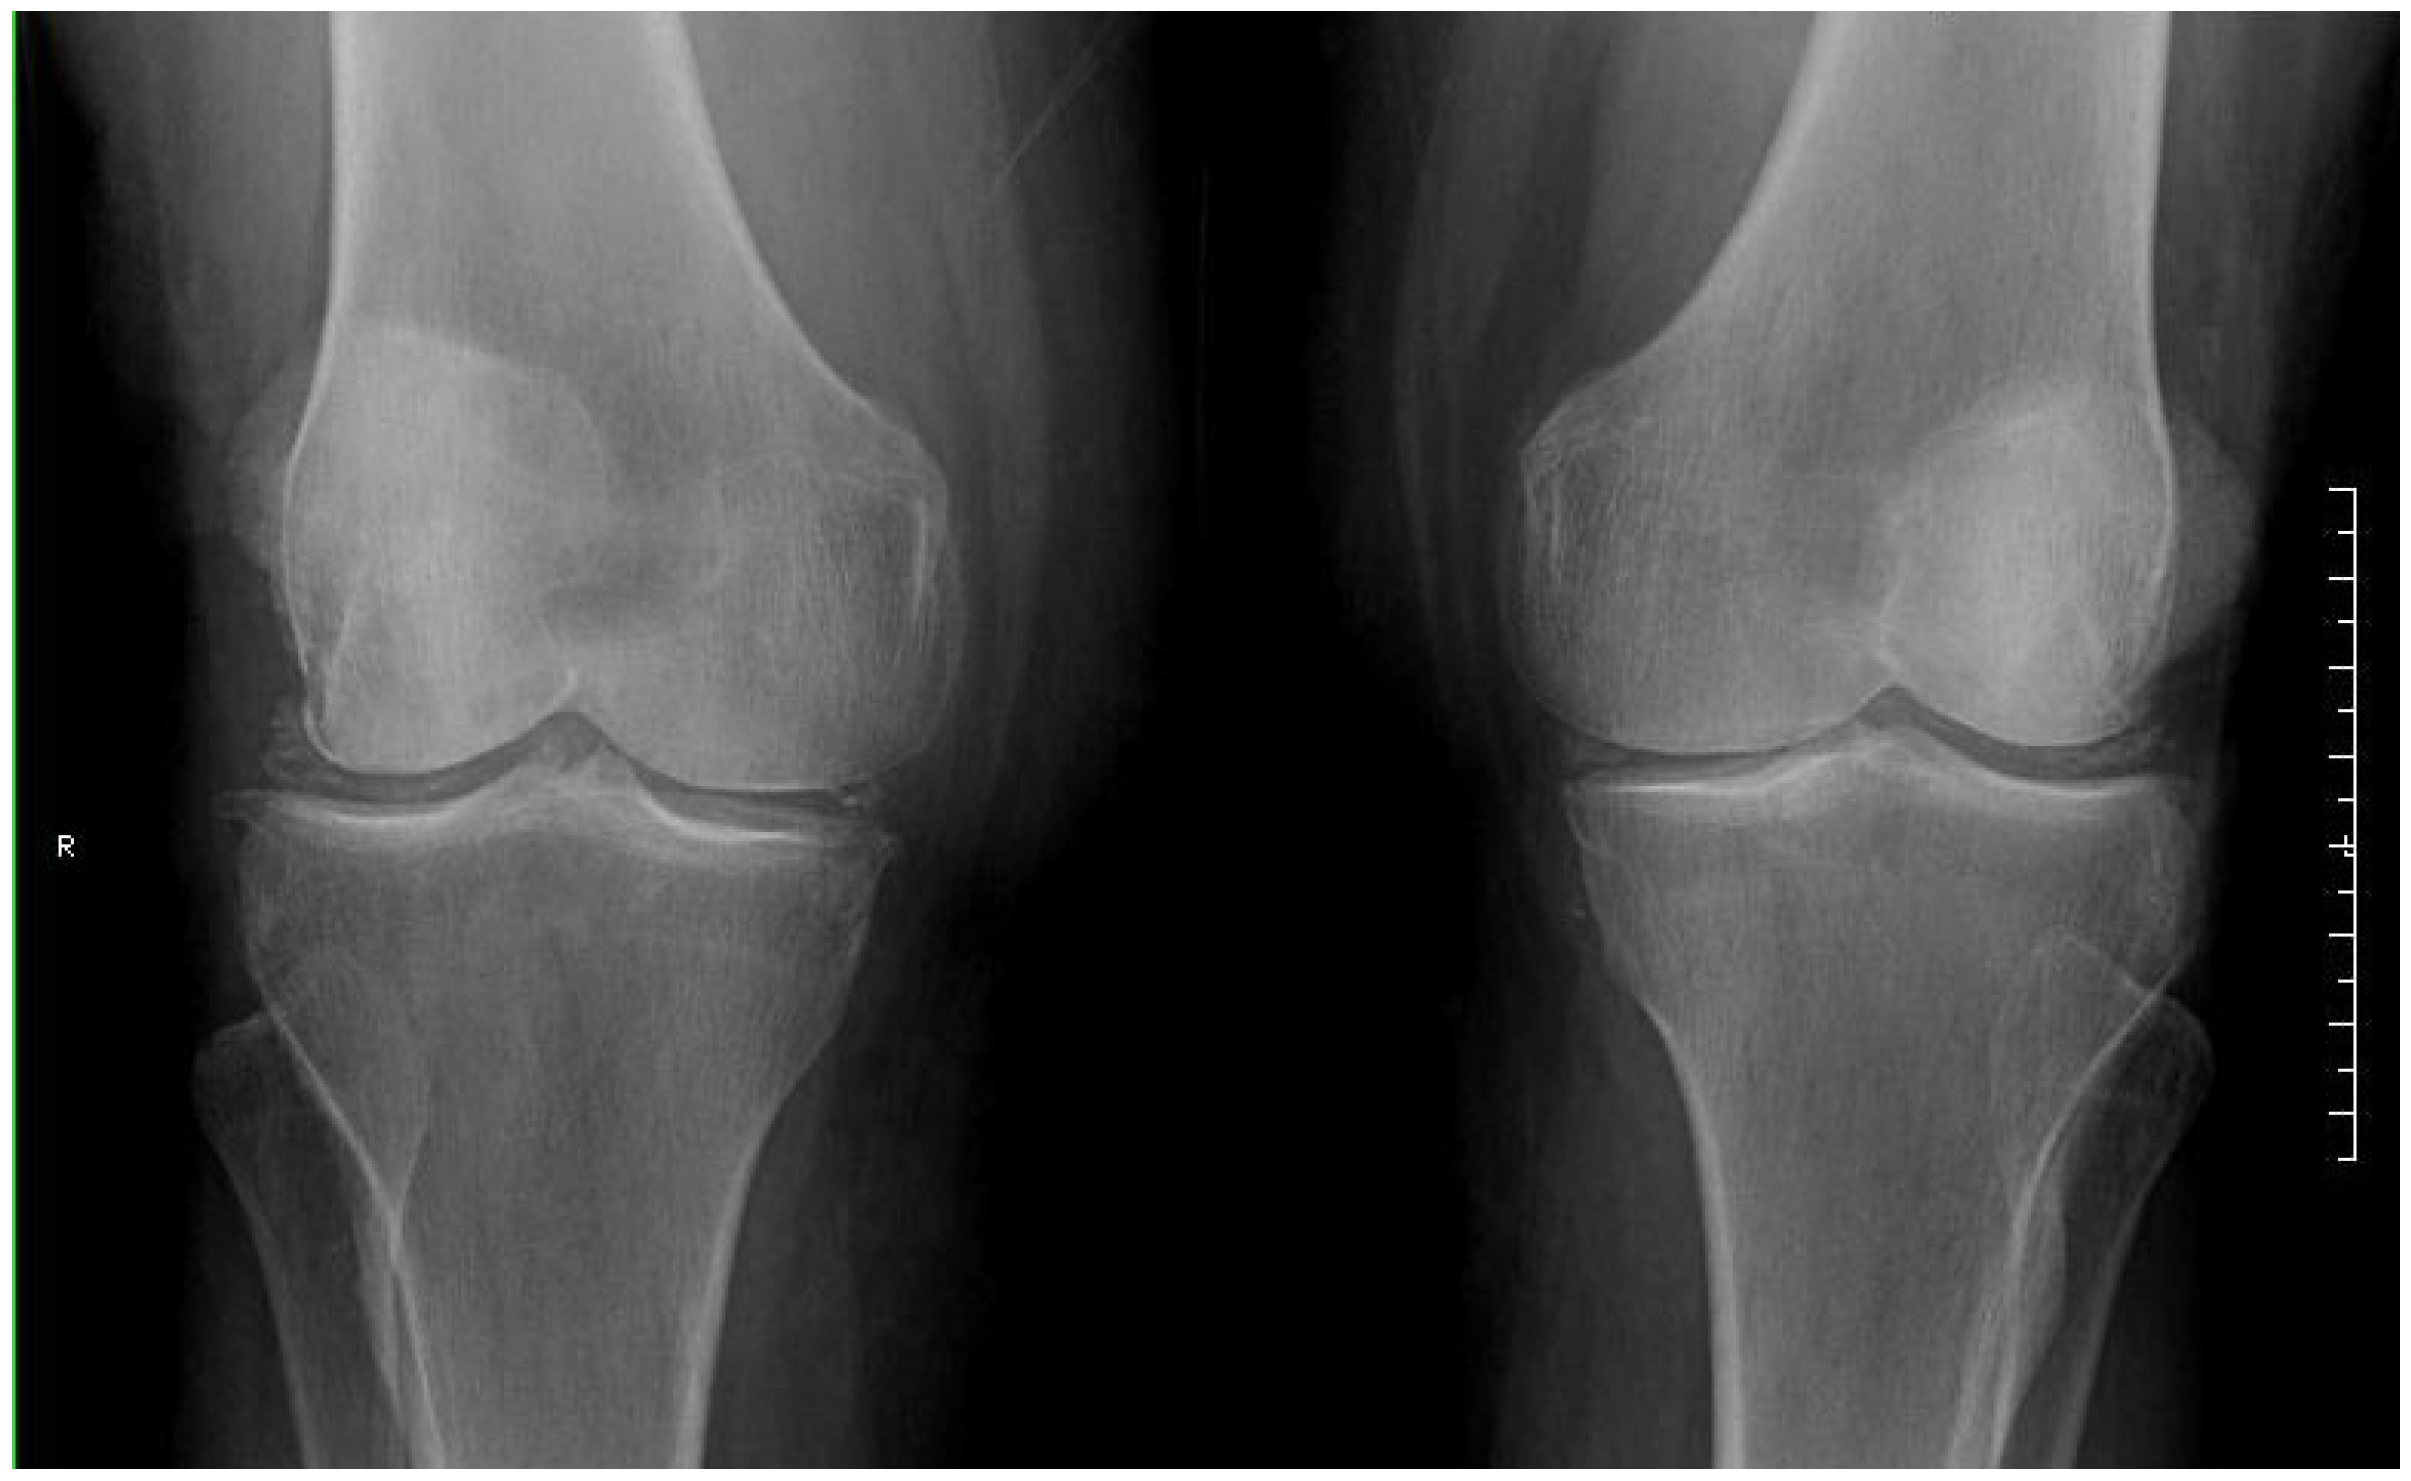

2. Detailed Case Description